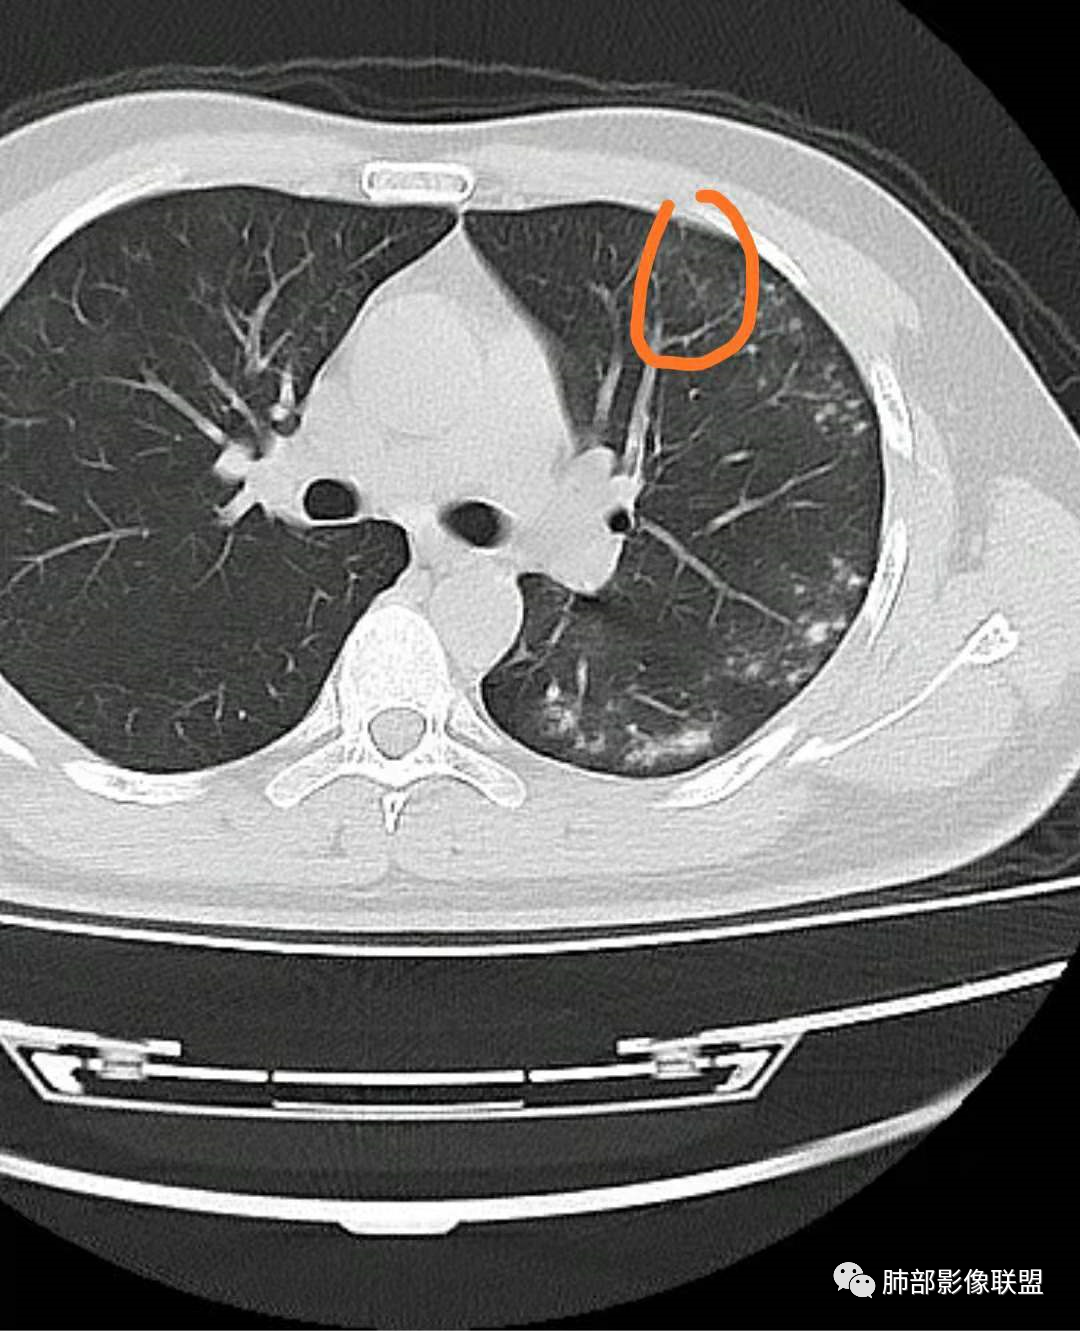

我们科里读片的时候,也是觉得主诉特别像PCP的主诉。但是影像学表现,双肺胸膜下多发小结节,结节周围带晕,蘑菇兄弟手拉手,有的结节侧向融合整体与胸膜平行。影像符合隐球。我们科里艾滋合并隐球菌真正确诊出来的很少。所以要说总结HIV合并隐球的病例特点,我没有发言权

肺隐球菌多分布在肺野外带或胸膜下区域,下叶多见,可能余隐球菌更容易在胸膜下肺泡中定植或蔓延有关;显示腺泡结节,然后取决于宿主免疫,可以入血,然后血播

如果是血播是随机分布,他这个是胸膜下

不是血道,就是直接吸入到远端肺泡

隐球结节的实质隐球菌自气道来,然后在支气管远端(呼吸性细支气管及肺泡)以及肺实质形成炎性肉芽肿结节

5、分布:病灶分布多位于胸膜下,可紧贴胸膜,也可与胸膜邻近,病灶长轴与胸膜平行。(划重点,分布特点非常重要)

10、“葫芦兄弟”:邻近胸膜多发结节,形态密度类似,可簇状分布,较少多形性,没有新旧不等。